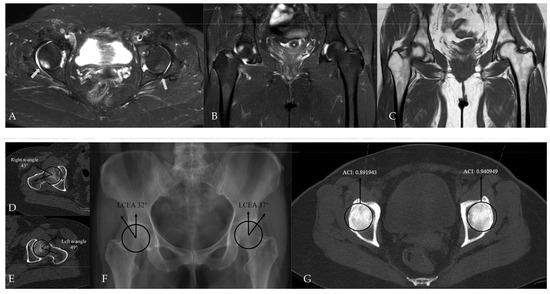

Figure 7.

Hip MRI demonstrates focal bone marrow edema in the anterolateral aspect of the right femoral head on (A) axial (white arrow) and (B) coronal fat-suppressed T2-weighted images. (C) Coronal T1-weighted image shows no underlying structural abnormality. (D,E) CT demonstrates normal alpha angle measurements. (F) LCEA measurements indicate pincer-type femoroacetabular impingement only on the left side. (G) However, using an ACI cut-off value of 0.93, bilateral pincer-type femoroacetabular impingement can be demonstrated.